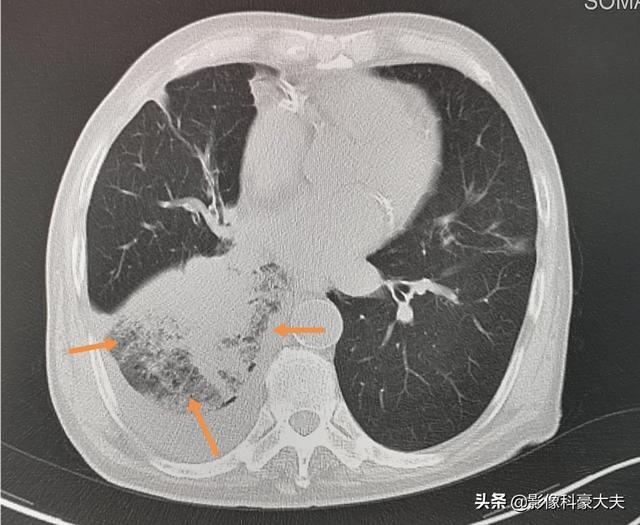

Es handelt sich um einen 79-jährigen Mann, der seit vier Jahren an kleinzelligem Lungenkrebs leidet, weil der rechte Unterlappenbronchus verengt ist, was eine obstruktive Lungenentzündung und wiederkehrendes hohes Fieber verursacht, ein Zustand, der auch tödlich sein kann, wenn die Infektion nicht unter Kontrolle gebracht wird, und der alte Mann ist derzeit in gutem Zustand.